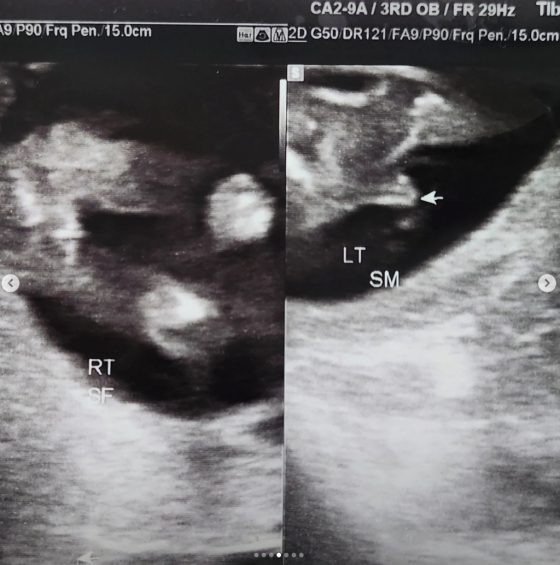

정인영은 초음파 사진을 올리며 "정말 감사하게도 왕자님과 공주님을 함께 만나게 됐다"라고 밝히고 "나이 마흔에 다태아. 이것만으로도 저는 이미 고위험 산모지만 아직까지는 씩씩하게, 또 매일매일 즐겁게 잘 지내고 있다"라고 전했다.